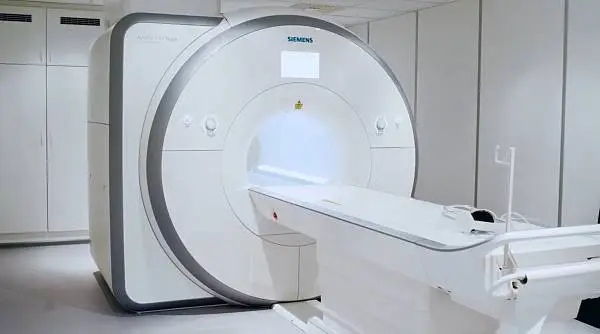

Используем самое современное оборудование для проведения МРТ - SIEMENS MAGNETOM Skyra - 3 Тесла (64 среза, 48 каналов)

Получите исключительно точный диагноз на одном из самых передовых и современных аппаратов с магнитным полем 3 Тесла

Мощность томографа влияет на расстояние между сделанными снимками. Чем меньше шаг исследования, тем выше вероятность выявления мельчайших изменений внутренних органов и тканей. Аппарат делает срезы размером в 1 мм, что позволяет обнаружить даже слабо проявляющиеся признаки развивающихся патологий на самых ранних стадиях и исследовать любые органы и ткани.

Аппарат мощностью в 3 Тесла позволяет уточнить диагноз, выявить изменения, возникшие на фоне лечения, подтвердить прогрессирование заболевания.

На диагностику с помощью томографа SIEMENS MAGNETOM Skyra 3 Тесла уходит в 1,5-2 раза меньше времени, чем при проведении исследования на аппарате мощностью в 1,5 Тесла.

Томограф позволяет получить качественные изображения в трехмерном формате с высокой разрешающей способностью и без посторонних шумов.

С помощью высокопольного томографа с индукционной мощностью в 3 Тесла проводятся обследования даже шишковидной (в головном мозге) и вилочковой (в грудной клетке) желез. Это зоны особого риска — они подвержены образованию микроскопических опухолей и кист. Для высокоточной диагностики требуется получить максимально тонкие срезы. С этой задачей справляется только самая мощная аппаратура в 3 Тесла.

Мы используем систему подавления акустического шума для большего комфорта во время исследования, а также подсветку MoodLight® для создания успокаивающей атмосферы

Преимущества и основные отличия от аналогичных аппаратов предыдущих поколений

- Максимально четкое изображение

Напряженность магнитного поля 3 Тесла позволяет исследовать наиболее глубокие слои тканей и органов без потери точности и создавать четкое, информативное изображение. - Никаких ограничений

Наш аппарат оборудован столом с высокой грузоподъемностью, благодаря чему мы можем проводить процедуру МРТ для пациентов с большим весом (до 250 кг). - Подходит для самых маленьких пациентов

Мощность нашего аппарата в 3 Тесла позволяет получить высококачественное изображение за более короткое время, что облегчает проведение процедуры МРТ для детей.

- Высокоточная детализация

64-срезовая технология сегодня является революционной, так как обеспечивает высокоточную детализацию изображений и позволяет регистрировать даже мельчайшие признаки патологии, что дает возможность диагностировать онкологические заболевания на самых ранних стадиях! - Технология Tim 4G

Это уникальная разработка компании SIEMENS, которая изменила МРТ. Благодаря ей пропала необходимость в смене позы у пациента при исследовании нескольких областей тела, а также стала возможной высокоточная визуализация процессов в реальном времени.

Вышеперечисленные особенности позволяют максимально точно создавать компьютерную модель тканей мозга, отображающую нарушения структуры и позволяющую ставить правильный диагноз на основе объективных данных. Это самое современное оборудование для выполнения МРТ головного мозга в Москве. Если вам необходим предельно точный и объективный результат, то его обеспечит обследование в нашей клинике.